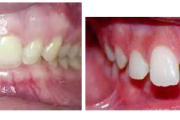

Normaalse jäävhammaskonna pilt küljelt ja eest vaadatuna.

Ravijärgne seis. Jäävhammas on täielikult lõikunud.